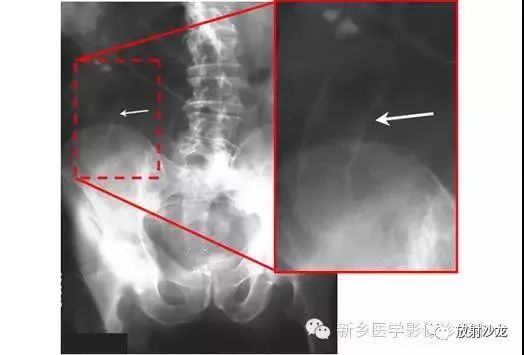

上图为一58岁男性,因1周前非特异性消化不良,行上消化道钡餐检查,做的腹部平片。患者最初表现为不确切的腹部不适和便血。现在又出现了腹痛和腹膜炎。箭头所指的典型表现是什么,诊断是什么?

箭头指向缺血穿孔性肠病患者的浅浮雕征。这也被称为双壁征或Rigler征。通常仅一侧肠壁可以看到。当双侧都能看到时,它表示腔内和腔外都有气体。当病人腹痛症状逐渐加重,肠壁穿孔是很有可能的。该患者手术过程中发现肠道脾曲缺血穿孔性肠病。